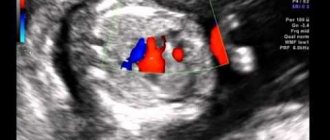

При плановой контрольной эхокардиографии через 6 мес после операции выявлено КДР ПЖ 1,8 см, ПП 4,4×3,8 см, ФИ 67%, область МПП интактна, визуализируется подвижное объемное образование ПП на ножке (2,5×1,7 см), пролабирующее в трехстворчатый клапан (рис.1).

Рисунок 1. Трансторакальная эхокардиография сердца пациентки К. В полости правого предсердия визуализируется объемное образование.